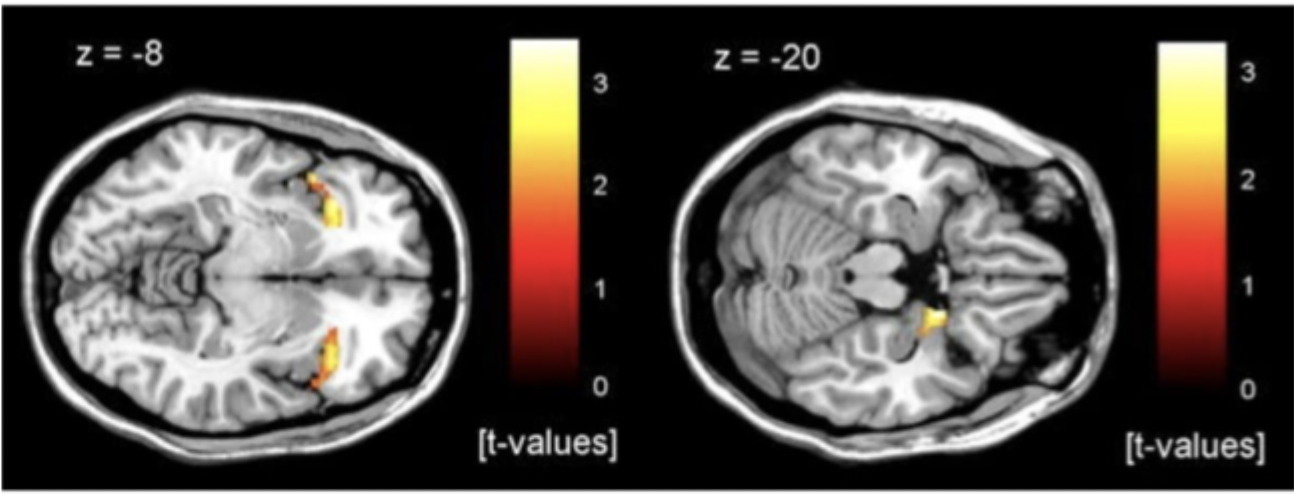

What did Dresler et al find in their study of patients who suffered panic attacks in the fMRI scanner leading to termination of testing?

What were the results for the first patients who was removed at the beginning of discomfort?

not a full panic attack: only observed a decrease in prefrontal cortex activity

decline in top-down control

suggest there is a top-down cognitive component in the onset of panic attacks

what were the results for the patients who was in full panic attack before being removed

demonstrated significant insula and amygdala activity

insula activity linked to feelings of discomfort

amygdala related to feelings of panic